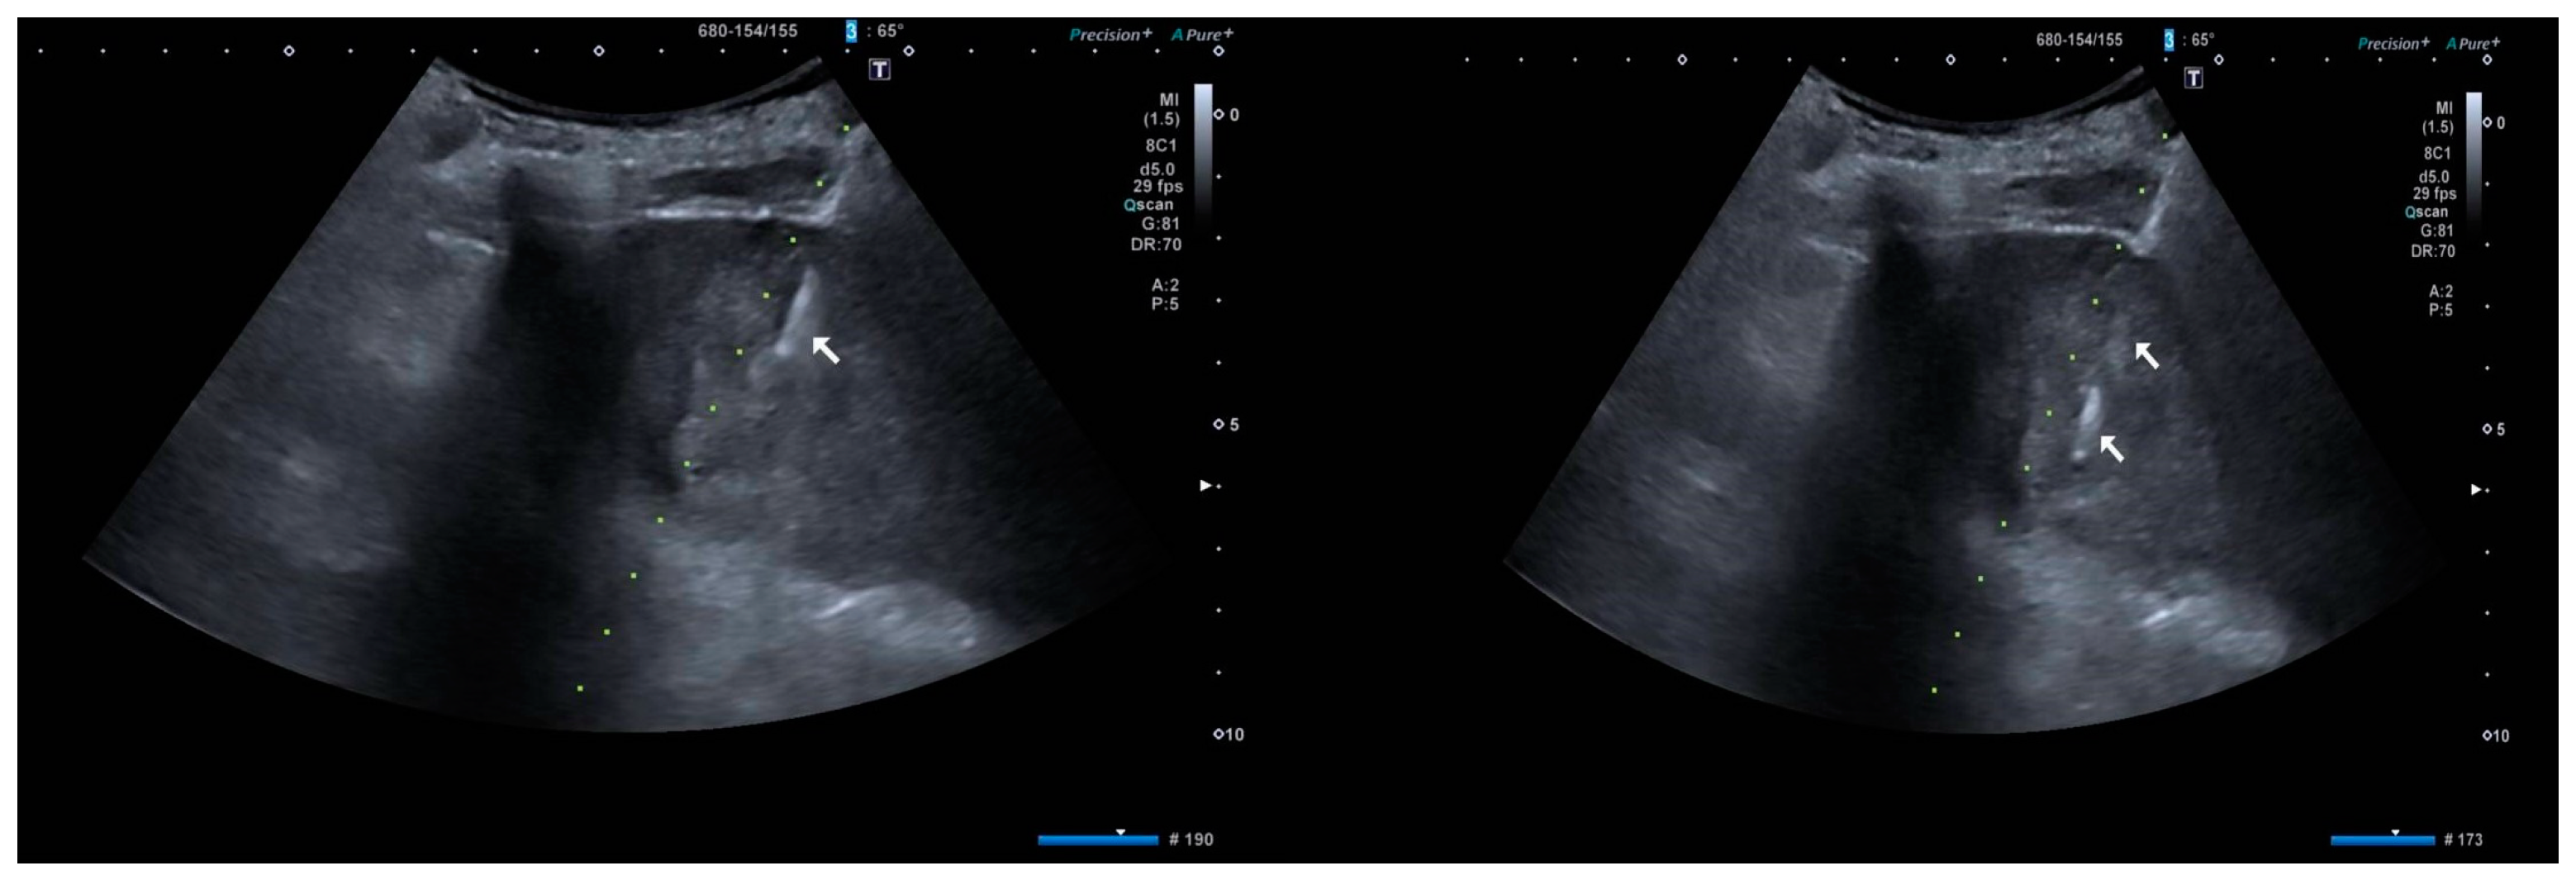

2. Case Presentation